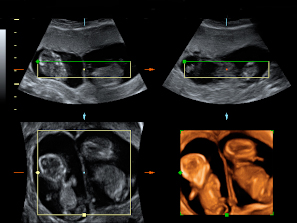

Los movimientos de estos gemelos de 12 semanas de gestación son extraordinariamente claros en la ecografía 4D. Los bebés mueven todo su cuerpo, especialmente brazos y piernas, adoptando multitud de posturas. Destaca el aspecto fieramente humano de los fetos, a pesar de su diminuto tamaño. Cuentan con dos placentas y dos bolsas independientes; la gruesa membrana de separación entre los bebés es visible en el registro ecográfico.

Ecografía 4D de gemelos de 12 semanas moviendo sus extremidades